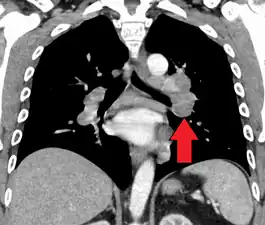

Hilar adenopathy especially on the person's left (AP CXR)

Hilar adenopathy especially on the person's left (lateral CXR)

Hilar adenopathy especially on the person's left (coronal CT)

Hilar adenopathy especially on the person's left (transverse CT)